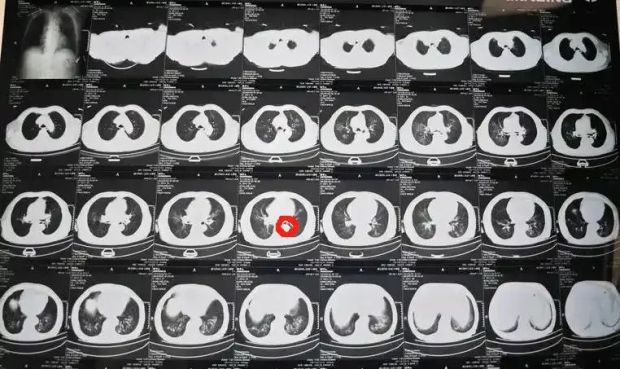

嘶,可能有點問題。我快速調整了片子的方位,把片子放在看片器上,打開了燈泡。

老司機,直接看降主動脈,放在左邊就對了。

紅色圈出來的就是降主動脈(示意圖,非該病人CT)

我看到病人左下葉一個很大的結節,混雜磨玻璃形態,中間有實性成分,第一感覺就是不好的。